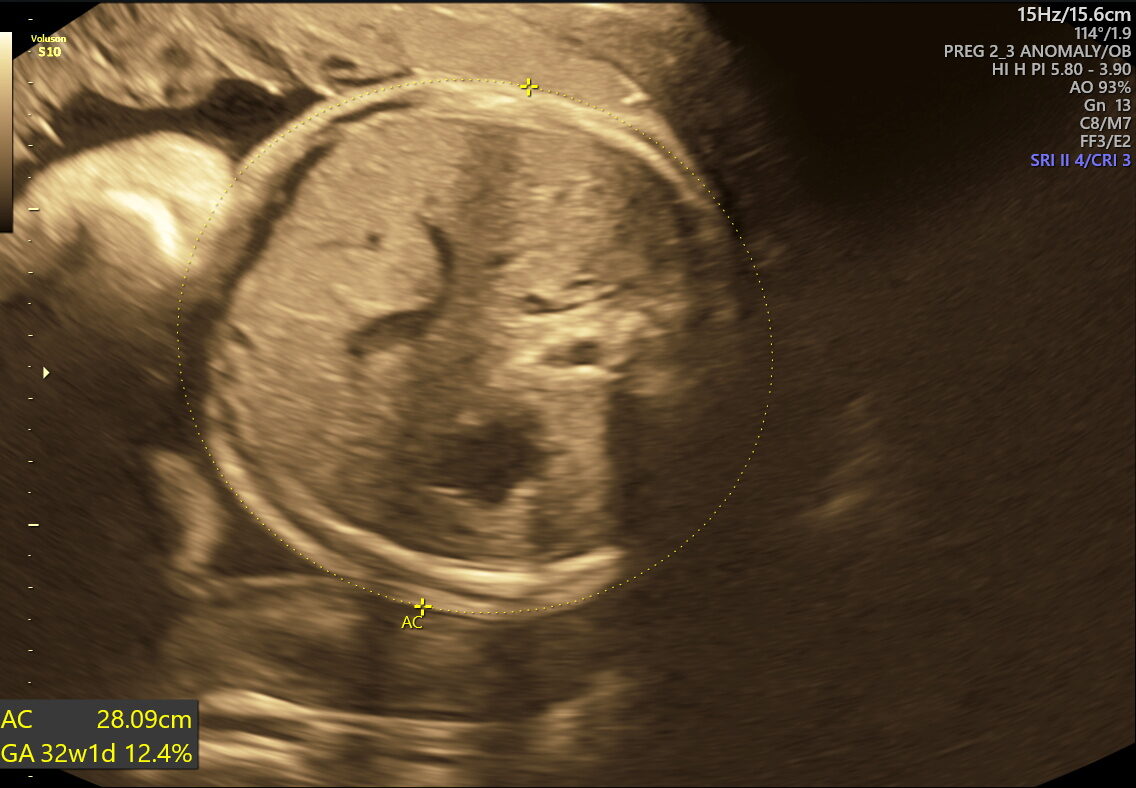

- Fetal Growth & Weight: Verifies if your baby’s size and weight meet healthy expectations for their gestational age.

This scan focuses on confirming birth readiness and spotting sudden issues that may arise close to your due date. It includes detailed Doppler studies to check blood flow in the umbilical cord and brain, ensuring your baby gets enough oxygen and nutrients.